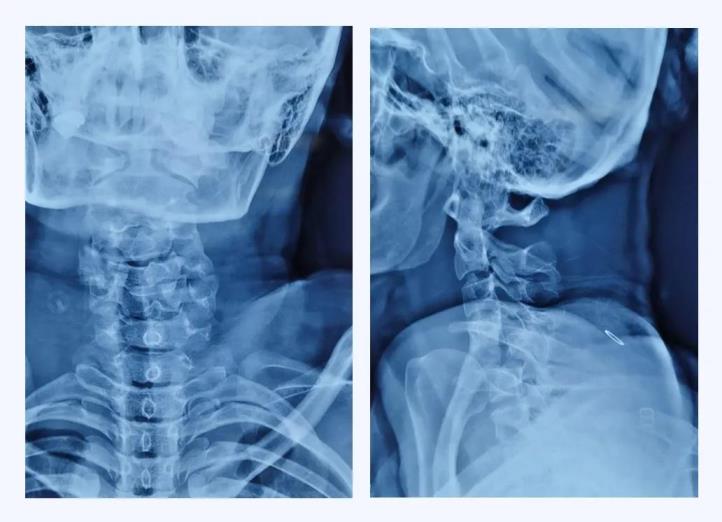

術(shù)前X線

經(jīng)查,病人確診為“頸椎骨折脫位 、頸髓高位損傷四肢癱”,以致四肢感覺運(yùn)動(dòng)均喪失。第五頸椎椎體完全脫位于后方椎管內(nèi),頸脊髓損傷嚴(yán)重,這類損傷導(dǎo)致脊髓水腫向上蔓延,可殃及呼吸循環(huán)控制中樞,患者隨時(shí)都有呼吸循環(huán)驟停危及生命的風(fēng)險(xiǎn)。我院骨科首席專家、業(yè)務(wù)院長喬建民教授聞?dòng)嵹s到醫(yī)院進(jìn)行緊急救治。一般的頸椎骨折脫位,只需將脫位的椎體復(fù)位并固定即可,但該患者由于脫位的第5頸椎椎體完全脫位至椎管內(nèi),導(dǎo)致相應(yīng)節(jié)段頸脊髓受到嚴(yán)重?cái)D壓、損毀、變形,已無法手術(shù)將其復(fù)位,只能選擇切除。手術(shù)部位是高位頸脊髓神經(jīng),并緊鄰椎動(dòng)脈,稍有不慎就會(huì)加重?fù)p傷,危及生命。手術(shù)難度之高、風(fēng)險(xiǎn)之大,是可想而知的。要完成這臺如此高難度的手術(shù),不單單是對術(shù)者技術(shù)能力的考驗(yàn),更是對醫(yī)者心智和意志的挑戰(zhàn)。